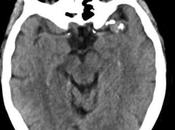

Glioma de alto grado

Caso clínico: Paciente femenino de la quinta década de la vida que acudió por presentar cefalea persistente así como hemiparesia corporal izquierda no densa... Leer el resto